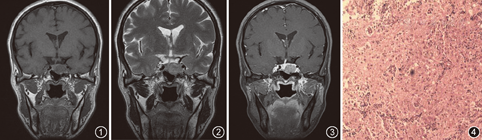

患者女,50岁,2年前无明显诱因出现双眼视力下降,未引起重视;3个月前出现头晕,于2017年11月16日就诊于我院。体检:神清目明,双侧瞳孔等大等圆,直径约3.0 mm,对光反射灵敏,粗测双眼视力下降。余神经系统查体未见明显异常。生长激素(GH)10.595 ng/ml(正常值0.010~3.607 ng/ml)。鞍区MR平扫及增强:蝶鞍扩大,鞍底下陷,鞍内左侧可见结节样团块状异常信号影,与垂体分界欠清,大小约1.8 cm×2.0 cm×1.4 cm,T1WI呈稍低信号(图1),T2WI呈不均质稍高信号(图2),增强扫描强化不均匀,强化程度低于正常垂体(图3),病灶累及左侧海绵窦,紧邻左侧颈内动脉,垂体柄略向左偏,视交叉走行良好,印象诊断为垂体腺瘤。

手术及病理:肿瘤位于鞍内,呈灰褐色,与正常垂体组织粘连,质地软,血运丰富,在显微镜下游离肿瘤边缘,分块切除肿瘤,并采用负压吸引将残余肿瘤完全吸走。肿瘤送病理检查:肉眼见淡褐色碎组织1堆,镜下见星形细胞与神经节胶质细胞混杂排列(图4)。免疫组织化学检查显示:增殖指数(Ki-67)约+3%,抑癌基因P53(-),突触素Syn(+),酸性钙结合蛋白S-100(+),胶质纤维酸性蛋白(GFAP)灶状+,异柠檬酸盐脱氢酶1突变体(IDH1R132H)-,少突胶质细胞转录因子(2Oligo-2)-,06-甲基鸟嘌呤-DNA甲基转移酶(MGMT)<10%,髓鞘碱性蛋白(MBP)-,微管相关蛋白(2Map2)+,嗜铬蛋白(CgA)部分+,抗神经元核抗体(NeuN)散在+。最终病理诊断:节细胞胶质瘤(Ganglioglioma,GG),WHO Ⅰ级。